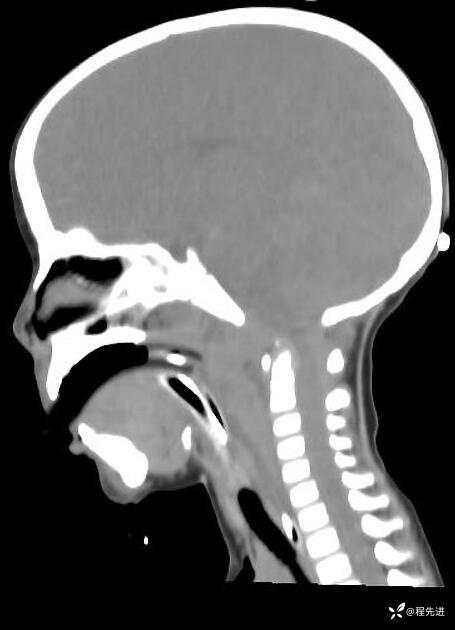

患者性别:男

患者年龄:5岁

简要病史:超速车祸外伤半小时

急诊CT平扫: